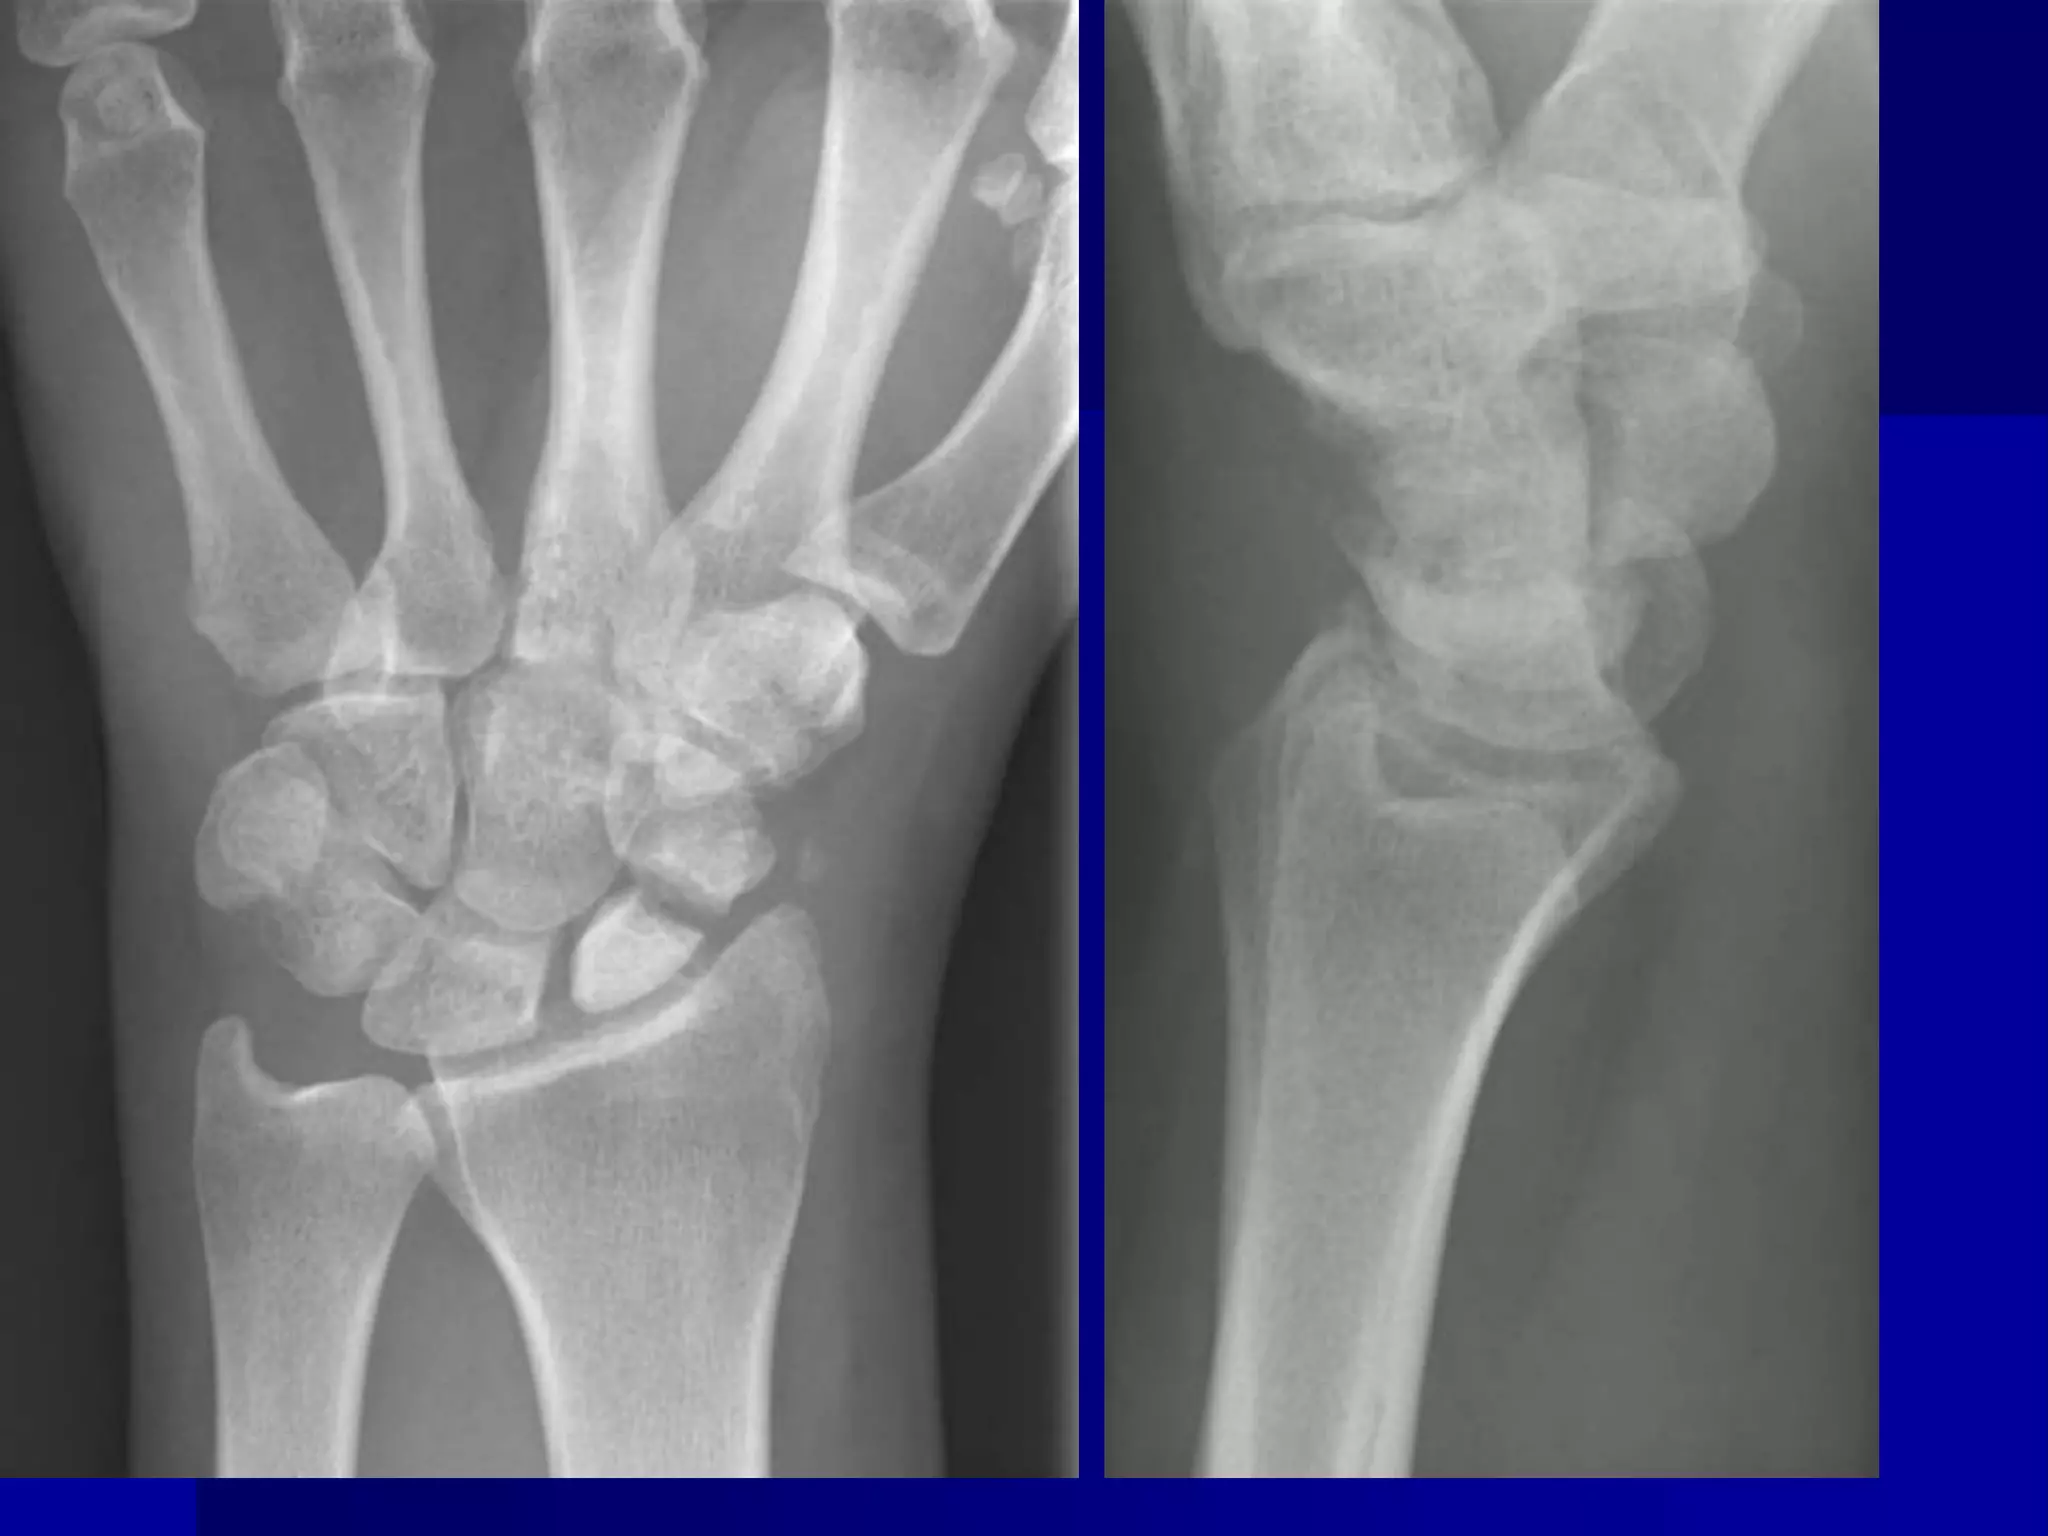

 Adult womanwith chronic left wrist pain. Avascular necrosis of the scaphoid bone. Age indeterminate scaphoid wrist fracture. Proximal scaphoid bone is sclerotic due to osteonecrosis.